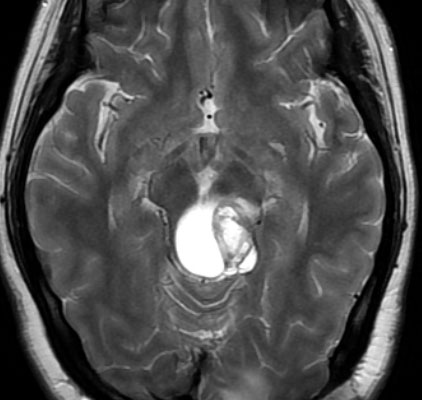

頭部打撲で検査され偶然発見された19歳男性ものです。中脳視蓋全体が腫大して腫瘍化しています。左側にのう胞があり周囲が淡くガドリニウムで増強されます。

中脳水道の癒着閉塞により,高度の停止性水頭症になっています。高身長ですが頭囲が61cmありました。小さい頃から頭が大きいので家族も気にならないようです。数年以上あるいは10年近くの長期にわたってこの水頭症は変わらないのでしょう。

頭痛などの症状はなく,眼底所見も視神経乳頭の異常はありませんでした。無治療で経過観察をしています。認知機能も全く正常で,国立大学から大学院に進む予定です。